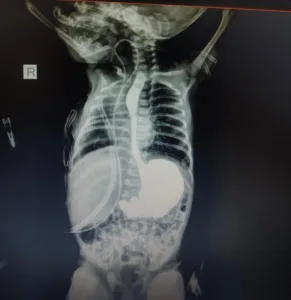

بعد انتهاء الجراحة، تولّى فريق الحضّانات متابعة الحالة بشكل مكثف، حيث تم وضع الطفلة على جهاز تنفس صناعي، ثم الانتقال إلى جهاز “سيباب”، وبعدها إلى وصلة أكسجين أنفية، حتى استقرت حالتها تدريجيًا على الهواء الطبيعي داخل المحضن، كما تم إجراء تصوير إشعاعي باستخدام الصبغة للتأكد من نجاح التوصيل بعد الجراحة، إلى جانب تقديم الرعاية التغذوية والتنفسية الدقيقة، ومراقبة الحالة على مدار الساعة لتفادي أي مضاعفات.